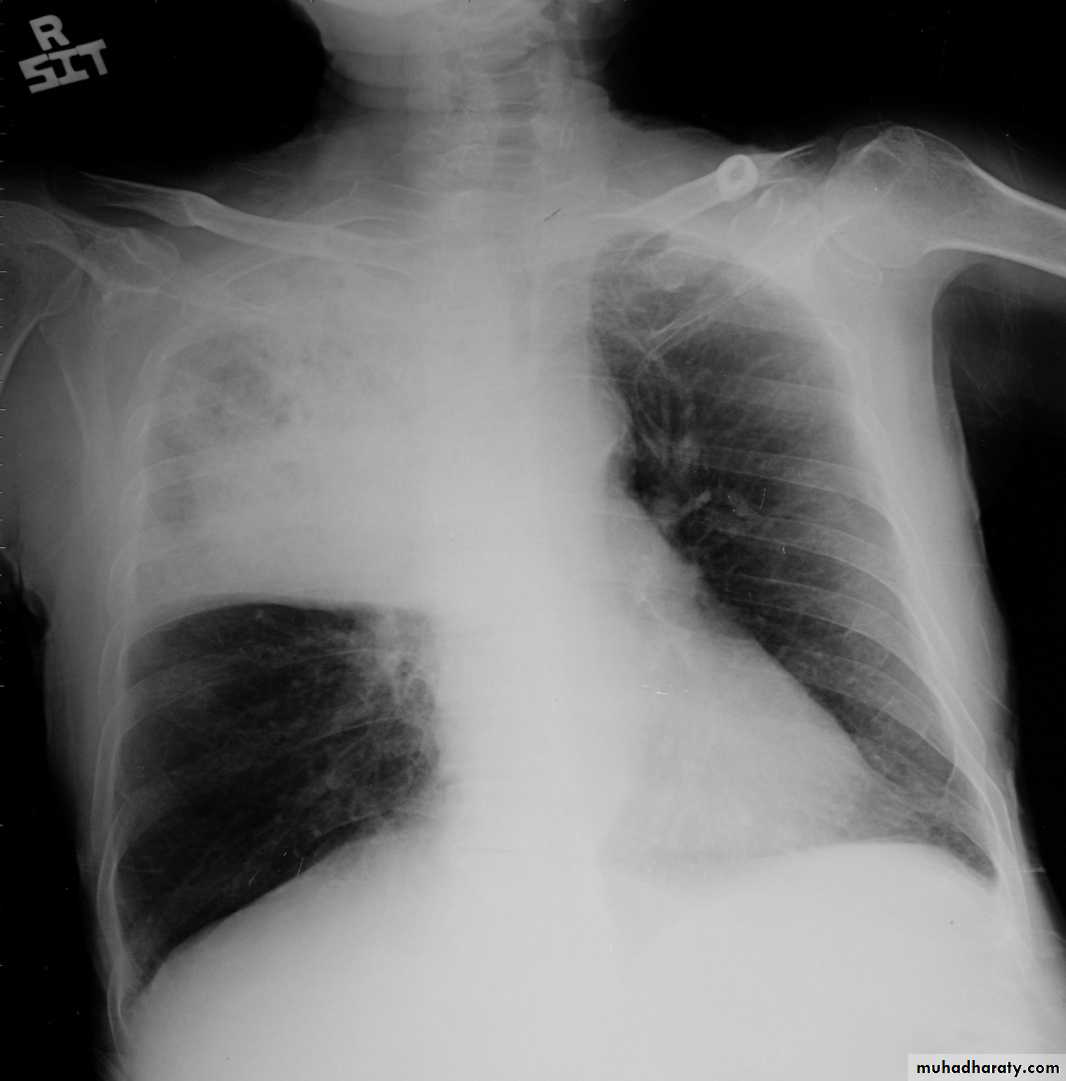

Left upper lobe collapse has distinctive features but can be challenging to identify on chest radiographs by the uninitiated.

Radiographic features

The left upper lobe collapses anteriorly becoming a thin sheet of tissue apposed to the anterior chest wall, and appears as a hazy or veiling opacity extending out from the hilum and fading out inferiorly . It thus reverses the normal slight increase in radiographic density seen as you move down the lung (due to increased thickness of the chest soft tissues).

Parts of the normal cardiomediastinal contour may also be obliterated where the left upper lobe, particularly the lingula abut the left heart border. The anterior parts of the aortic arch are also often obliterated from view.

In some cases the hyperexpanded superior segment of the left lower lobe insinuates itself between the left upper lobe and the superior mediastinum, sharply silhouetting the aortic arch and resulting in a lucency medially. This is known as the luftsichel sign.

The left hilum is also drawn upwards, resulting in an almost horizontal course of the left main bronchus and vertical course of the left lower lobe bronchus.

Non-specific signs indicating left sided atelectasis will also be present, including:

elevation of the hemidiaphragm

'peaked' or 'tented' hemidiaphragm: juxtaphrenic peak sign

crowding of the left sided ribs

shift of the mediastinum to the left

On lateral projections the left lower lobe is hyperexpanded and the oblique fissure displaced anteriorly. There is associated increase in the retrosternal opacity.